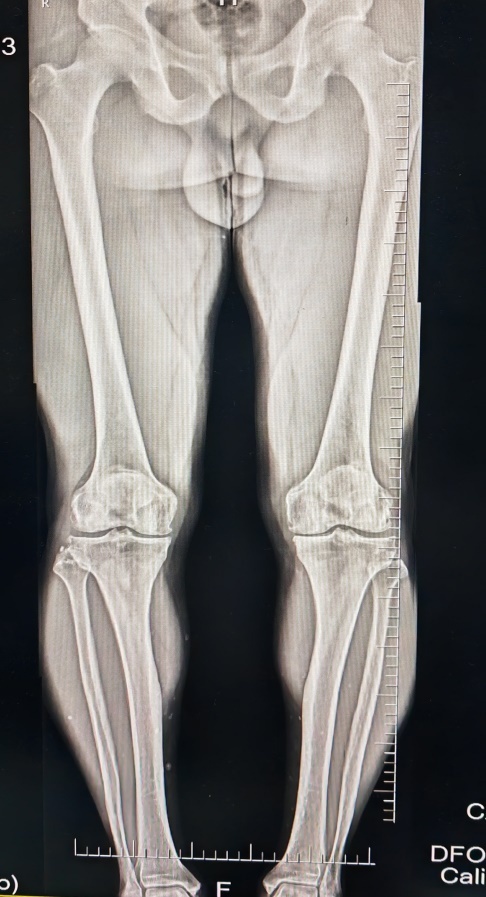

今年40岁的的张先生(化名),是永州市的一名体育老师,平时喜欢运动,酷爱篮球。向来身体健康的张先生,近日气温骤降之后,出现了不明原因的膝关节疼痛,症状逐渐加重,不但影响到其正常运动,日常生活行走时也感到膝关节疼痛难忍。张先生前往当地医院检查发现,左膝关节内侧半月板三度损伤、内侧软骨磨损严重,多处骨质增生。为了得到更优质的医疗服务,张先生来到湘南学院附属医院求诊。骨一科主任唐新文接诊患者,经过详细问诊查体并结合影像学检查,发现张先生除了关节损伤之外,还存在双下肢内翻畸形,即俗称O形腿,初步考虑双下肢力线不佳、过量的运动导致的膝骨关节炎。

通过双下肢站立位全长X片、MR等检查,结合张先生的年龄、工作性质、运动方式、骨性关节炎的程度等,唐新文团队确定其为膝骨关节炎Kellgren&Lawrence分级Ⅲ级。“该阶段的膝骨关节炎采用单纯的基础治疗和药物治疗效果并不理想,需行修复性治疗,考虑患者相对年轻,运动要求高,而目前膝关节退变情况又较重,还存在一定内翻畸形,我们综合评估下来,认为比较适合行膝关节镜清理、半月板成形+胫骨高位截骨术。”唐新文介绍,近年来“保膝”理念被广泛关注,胫骨高位截骨术在许多方面也有了新的认识和技术改进,通过截骨、矫正下肢力线,使膝关节骨关节炎部位的受力重新分布到膝关节的健康部位,以减缓膝关节的退行性改变,延长膝关节的使用寿命,减少了手术创伤,提升了疗效,对伴有力线不正(如O形腿或者X形腿)的骨关节炎,也是一种非常有效的治疗措施。